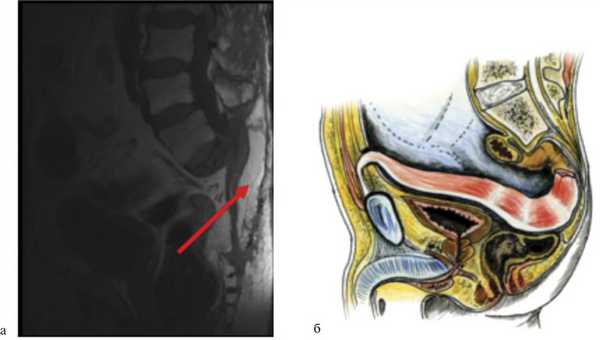

Показаниями к резекции крестца в 17 наблюдениях явились данные, полученные при предоперационном обследовании пациента (МРТ), — прорастание опухоли в крестец либо в пресакральную фасцию. У 15 больных решение о выполнении резекции крестца было принято интраоперационно при обнаружении сращения опухоли с крестцом и в связи с невозможностью, с точки зрения хирурга, отделить опухоль без опасного сближения с ее циркулярной границей.